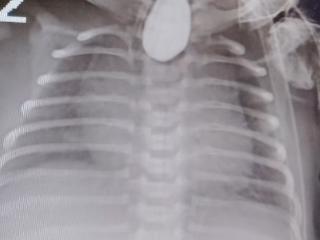

新生儿口吐白沫,山大附属儿医紧急为食管闭锁宝宝抢回“生机”